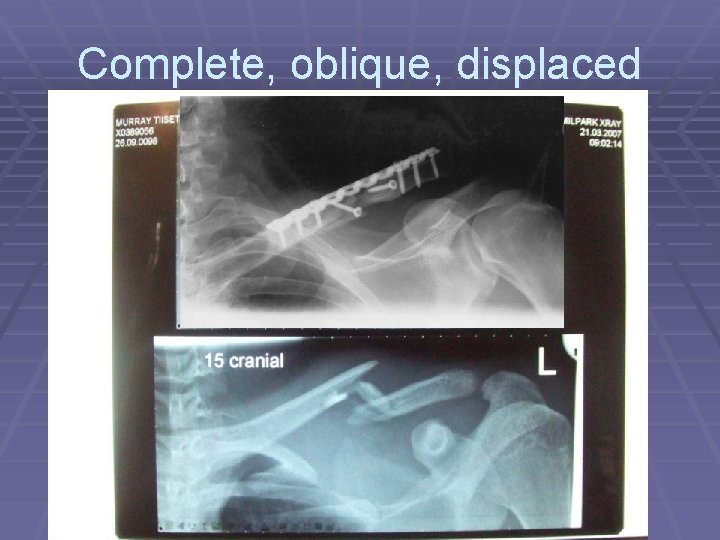

Complete, oblique, displaced